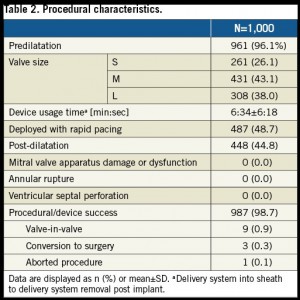

前拡張が96%で施行され、後拡張も45%で施行された。

手技成功はSmall 98.9% (n=258), Medium 98.4% (n=424), Large 99.0% (n=305) で得られた。